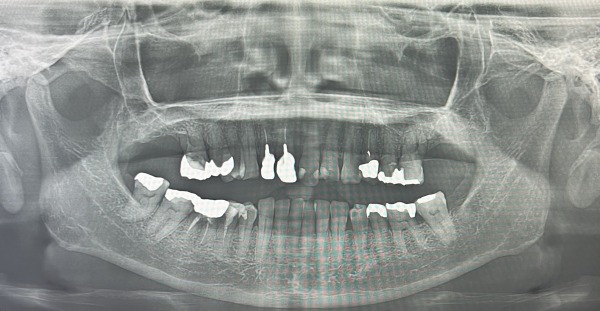

まず、虫歯の有無を調べ、詰め物などの記録をとります。続いて、レントゲン撮影を行い、歯周病の検査項目である歯周ポケットの深さ、歯の揺れ、磨き残しの付着度合いを調べました。その検査の際、前歯の被せ物が少し揺れていたため、追加で口腔内エックス線写真を撮影しました。

エックス線写真によると、前歯2本は神経を取り除いており、土台に「金属」を使用した差し歯であることが分かりました。被せ物と歯の間に隙間ができており、治療前の写真では歯が部分的に黒く変色しています。

よく見ると、2本とも根尖部のエックス線透過像はありませんが、細菌感染していることが考えられるので、根管治療から始めていくことにしました。